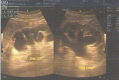

Results: Patient 1: A 58-year-old female had five episodes of acute left ureteral lithiasis in two years prior to left kidney tuberculosis. Patient 2: A 55-year-old male patient had a 1.2 cm proximal left ureteral stone and in the following six months, the diagnosis of tuberculosis was made in a nonfunctioning left kidney with ureteral thickening and stenosis. Patient 3: A 47-year-old male patient had a 1.2 cm stone in the proximal right ureter and developed urinary tuberculosis with a nonfunctioning right kidney and a contracted bladder.